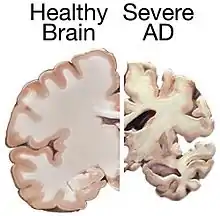

| Normal brain on left contrasted with structural changes shown in brain on right of person with Alzheimer's disease, the most common neurodegenerative disease[1] | |

Alzheimer's disease

Alzheimer's disease (AD) is a chronic neurodegenerative disease that results in the loss of neurons and synapses in the cerebral cortex and certain subcortical structures, resulting in gross atrophy of the temporal lobe, parietal lobe, and parts of the frontal cortex and cingulate gyrus.[11] It is the most common neurodegenerative disease.[1] Even with billions of dollars being used to find a treatment for Alzheimer's disease, no effective treatments have been found.[12] However, clinical trials have developed certain compounds that could potentially change the future of Alzheimer's disease treatments.[13] Within clinical trials stable and effective AD therapeutic strategies have a 99.5% failure rate.[14] Reasons for this failure rate include inappropriate drug doses, invalid target and participant selection, and inadequate knowledge of pathophysiology of AD. Currently, diagnoses of Alzheimer's is subpar, and better methods need to be utilized for various aspects of clinical diagnoses.[15] Alzheimer's has a 20% misdiagnosis rate.[15]